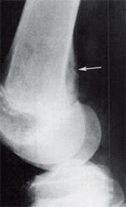

Fig. 3: Popliteus muscle.

The AP tunnel view demonstrates an accentuated groove (Fig. 2, white arrow) for the patellar tendon, which is a normal finding and should not be confused with erosion. The popliteus muscle origin is on the anterior portion of the popliteal groove on the lateral femoral condyle; a lesser origin is from the head of the fibula, and there is an additional origin from the lateral meniscus in a small percent of the population (Fig. 3). It courses under the lateral collateral ligament, descends into the popliteus hiatus, then passes under the arcuate ligament and becomes extra-articular before finally joining its muscle belly. It's insertion is fan-like on the posterior surface of the tibia above the popliteal line.